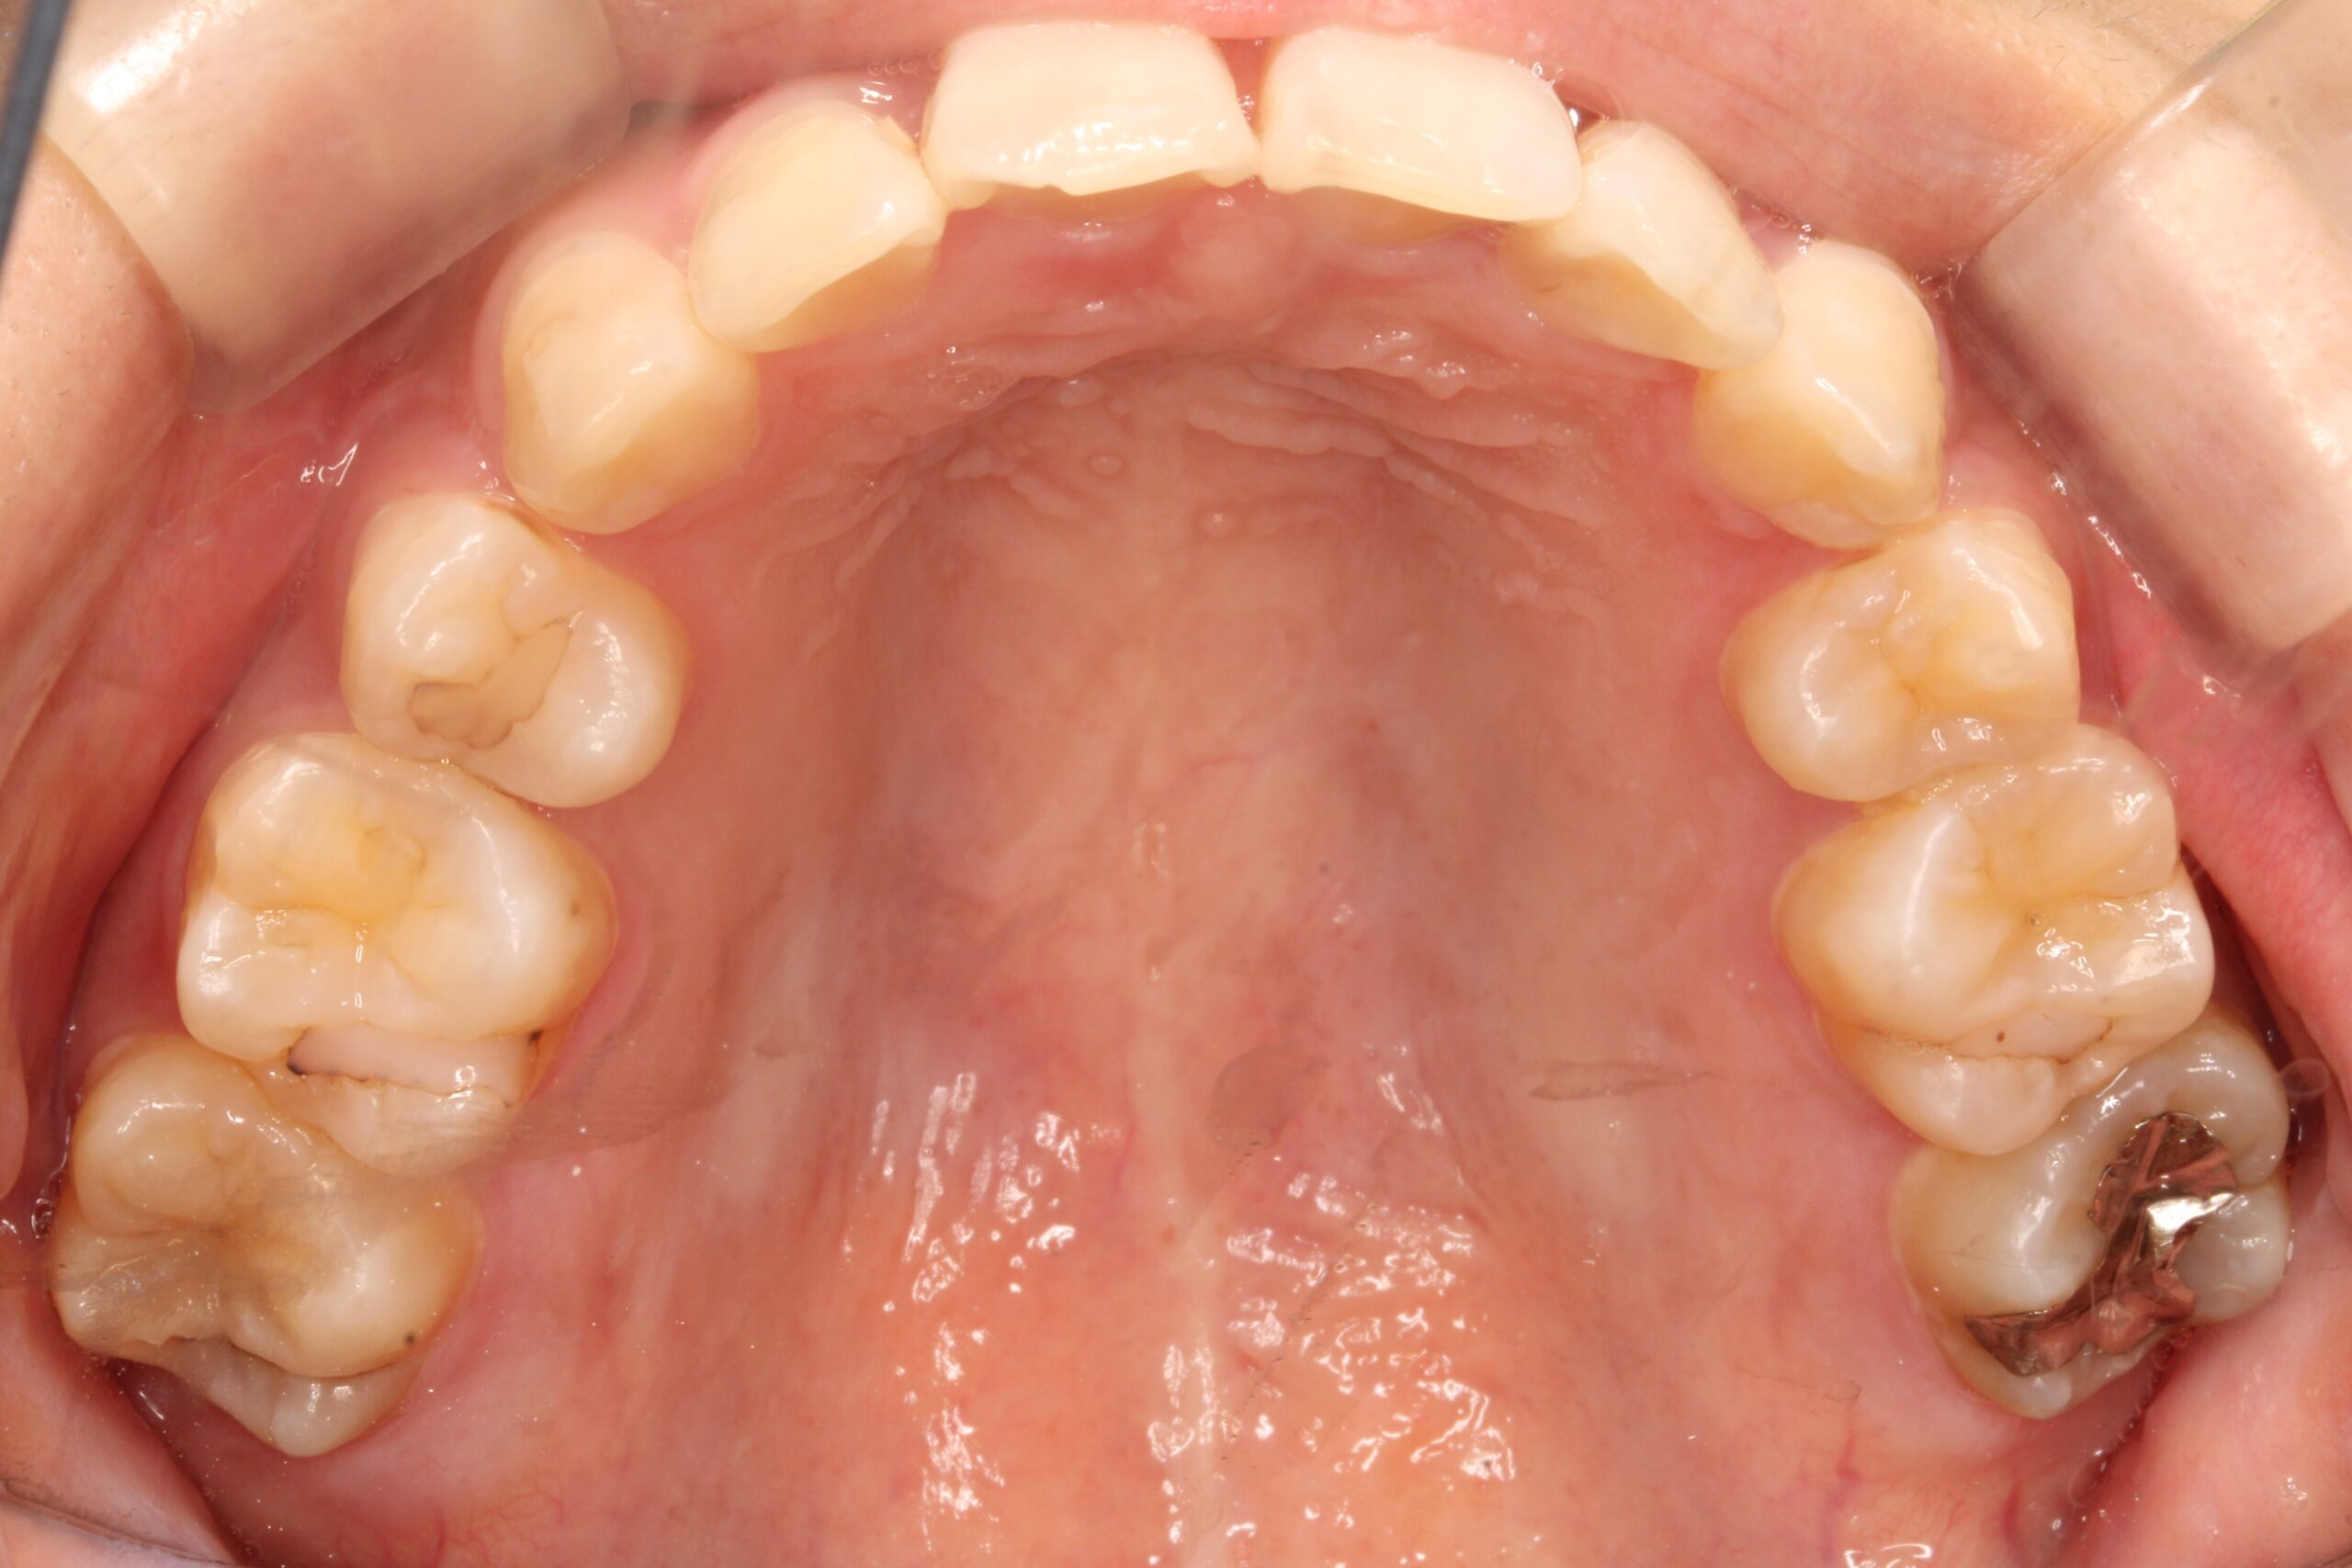

矯正術前:上顎

矯正術後:上顎